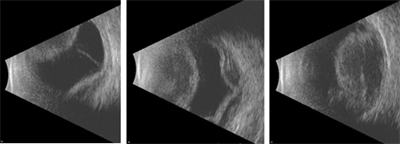

Your retina specialist will perform a detailed eye exam. Often, an ultrasound is helpful to document the size and composition of the choroidal detachment (serous, hemorrhagic, or mixed), and to follow the change in size over time (Figure 1).

An echographic (ultrasound) image of the eye shows a choroidal detachment. Your retina specialist can use these images to differentiate a choroidal detachment from a retinal detachment, characterize the size and type of the choroidal detachment (ie serous, hemorrhagic, or mixed), and monitor changes over time.